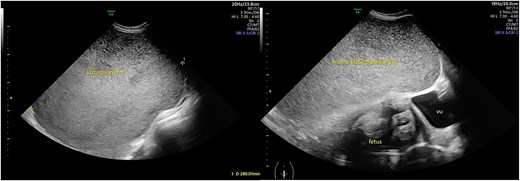

A 26-year-old woman with 34 weeks of gestational age, came to the polyclinic with the symptoms of right abdominal discomfort referred from another hospital with a massive ovarian cyst in pregnancy. The ovarian cyst was first detected during 28 weeks of pregnancy during her first ultrasound examination. Her abdomen was distended with a palpable mass until processus xiphoideus. Ultrasound examination showed the uterus was pushed to the right side of the abdomen with a singleton live fetal breech presentation. The fetus was around 34-weeks of gestational age, with estimated fetal weight of 2299 g, normal amniotic fluid index, and no Doppler abnormality. The ovarian cyst was unilocular from the left adnexa containing homogenous echogenocity fluid with a diameter of 28 cm, suspected of a mucinous cyst (Figs 1 and 2). A follow-up ultrasound examination showed a similar result for the cystic mass, however, the baby’s growth was declining. The Ca-125 value was below 15. Since the mass was suspected of benign origin, a Cesarean section (CS) was planned at term continued with unilateral salpingo-oophorectomy. There is no urgency to do a earlier termination of pregnancy since the fetus cardiotocography and doppler studies is within normal limit.

Ultrasound view of the cystic mass. The mass was unilocular without a solid part with a diameter of 28 cm.

Illustration of the giant ovarian cystic mass position according to the uterus.